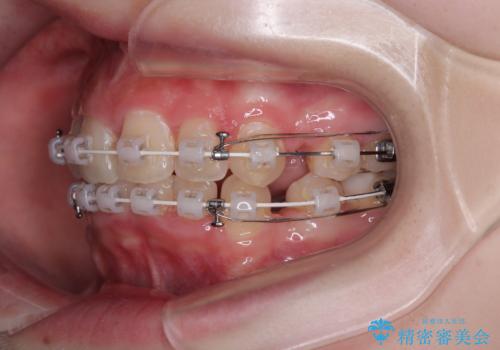

【モニター】デコボコと隠れてしまう前歯 ワイヤー装置による抜歯矯正で美しい口元に

- 審美装置

- デコボコになっている前歯を気にして来院された患者様です。

口元の突出感は気になっていないものの、デコボコを解消すると口元が前方に突出する可能性があるため、上下左右の第一小臼歯4本を抜歯して、ワイヤー装置にて矯正治療を行うこととしました。

下の前歯が隠れてしまうほど深く咬みこんでいたため、上顎前歯が前方に突出しているような印象がありましたが、咬み合わせが改善され、整った口元に仕上げることができました。